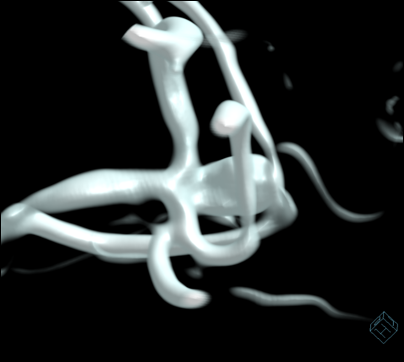

Mujer de 69 años con aneurisma incidental en la ACM.